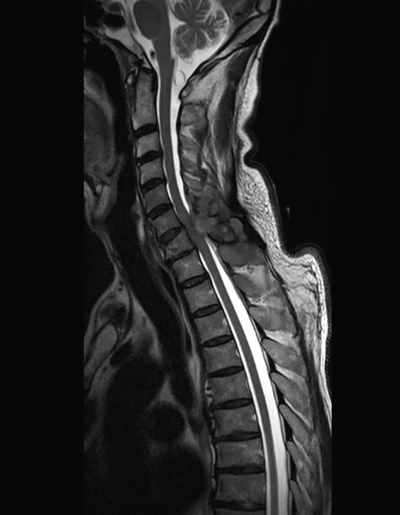

A 78-year-old man presented with a PSA of 2450ng/ml complaining of weakness in his legs and upper back pain. The sagittal MRI scan of his spine is shown below.

- What does this MRI scan show?

This MRI of the spine (saggital section) shows a lesion causing compression on the spinal cord at the level of C6.

Spinal cord compression in this setting is an acute oncological emergency. Failure to treat this condition promptly can result in permanent paraplegia and autonomic dysfunction. Initial urethral catheterisation and prompt administration of high-dose intravenous corticosteroids (e.g. a loading dose of 16mg dexamethasone followed by 4mg six-hourly), analgesia, bisphosphonates, and prophylactic gastric protection (e.g. proton pump inhibitor) is required. Urgent neurosurgical or oncological opinion should be sought for consideration of spinal cord decompression or radiotherapy.